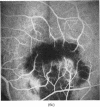

Development of senile disciform degeneration in the second eye was studied in a group of 104 patients over a period of up to five years. 12 to 15% of these patients develop disciform degeneration in the other eye each year. Patients with large and confluent drusen, especially if combined with accumulation of dye on fluorescein angiogram, were at greatest risk of developing disciform degeneration in the second eye.